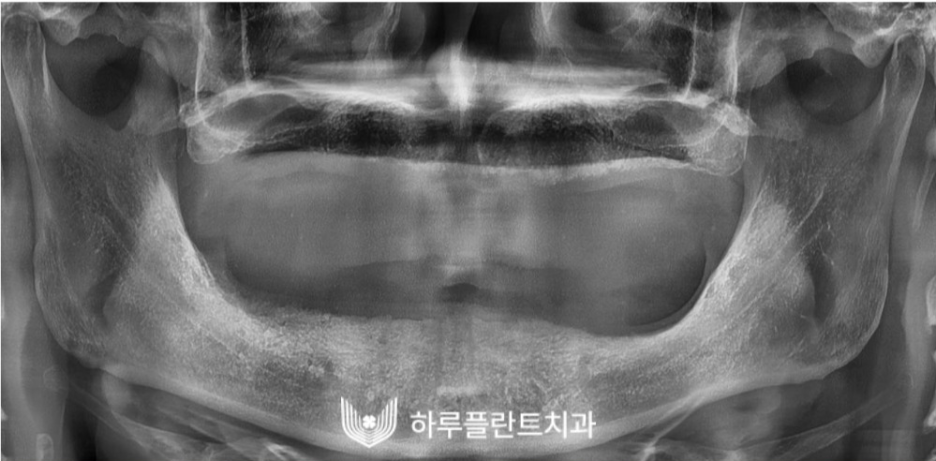

수술 성공 케이스 2

2021.08

다음은 치아가 하나도 없는

무치악환자분의 전악 임플란트 사례인데요.

이 분 또한 하치조 신경까지 거리가 매우 가깝고

상악동 골흡수가 매우 심해

임플란트 수술 불가 판정을 받고

하루플란트치과 를 찾아오셨습니다.

수술 전 구강 내 사진입니다.

잇몸뼈 흡수가 매우 심한 상태였습니다.

이 상태에서 임플란트를 식립할 경우

쉽게 흔들리거나 탈락할 수 있기 때문에

뼈이식을 우선적으로 진행해야 합니다.